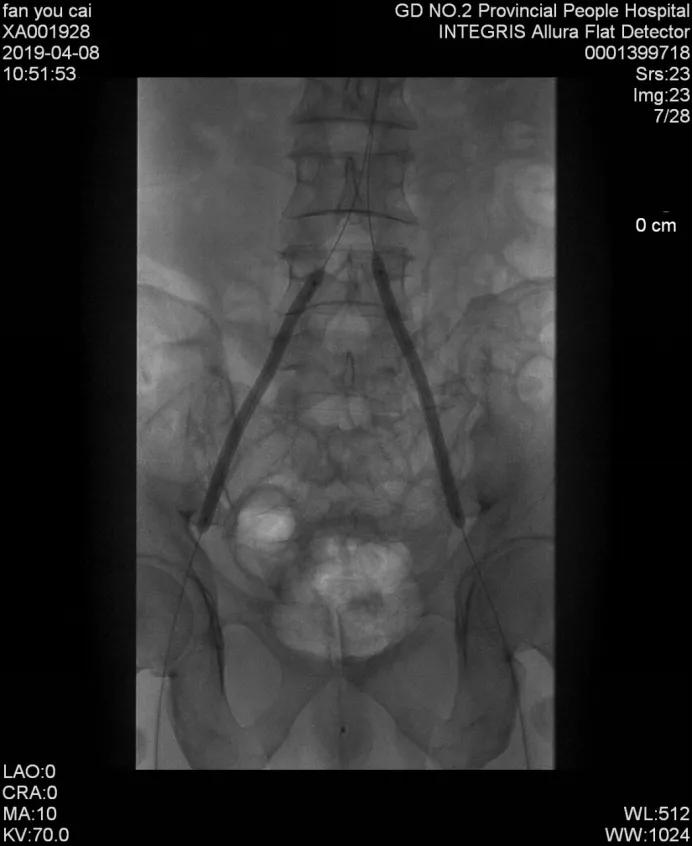

经过认真细致的讨论,最终给老樊确定了最优方案:左肾动脉、腹主动脉及髂股动脉支架植入术,手术是在一根只有针头粗的导丝引导下,将支架放入闭塞部位复通血管,不仅对患者的创伤小,而且双侧下肢可以同时进行手术,不用分两次,能省去一半的手术费用。

手术很快便安排上了,经过手术团队的努力,肖承江主任团队顺利给老樊完成了介入支架手术,术后患者腹部大血管、肾脏血管及下肢血管全部恢复通畅。